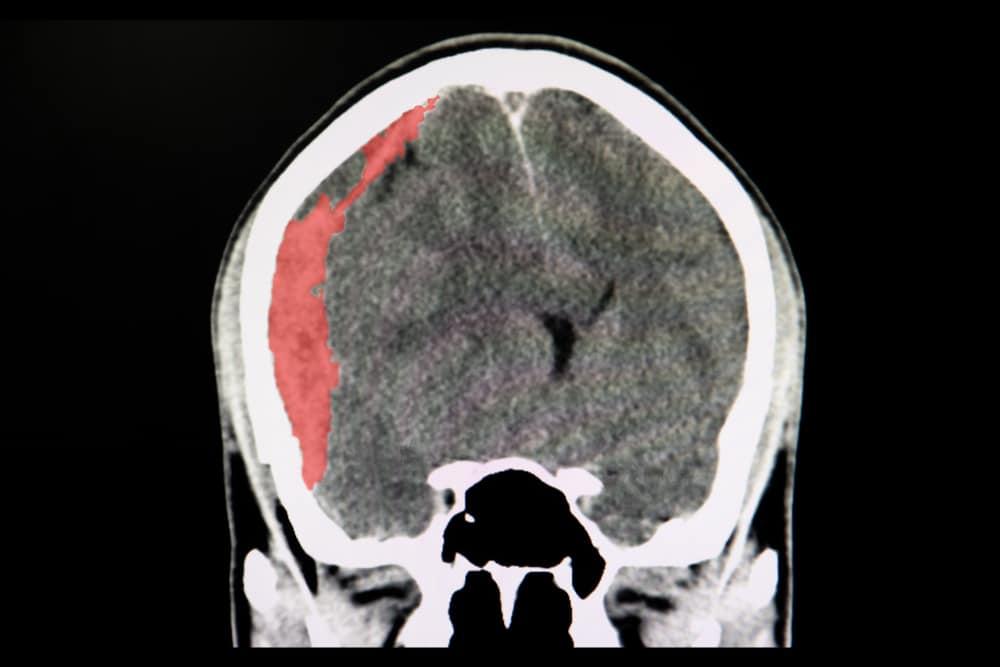

Não của con người được bao bọc bởi các lớp màng não, bao gồm màng cứng, màng nhện và màng mềm, sau đó mới tới xương sọ và da đầu. Khi mắc bệnh tụ máu dưới màng cứng (hay còn gọi là xuất huyết dưới màng cứng), máu sẽ bị tích tụ ở khoảng trống ở giữa màng cứng và màng nhện.

Bệnh có thể cấp tính (khởi phát nhanh) hoặc mạn tính (tiến triển từ từ). Tụ máu cấp tính hoặc quá lớn có thể gây tăng áp lực nội sọ, dẫn đến chèn ép và tổn thương mô não. Tình trạng này có thể đe dọa tính mạng người bệnh.

Người bệnh nhập viện sau khi bị chấn thương đầu thường được làm chẩn đoán hình ảnh đầu như chụp cắt lớp vi tính (CT) hoặc chụp cộng hưởng từ (MRI). Những kiểm tra hình ảnh này có thể giúp bác sĩ phát hiện sự tồn tại của tụ máu dưới màng cứng. Chụp MRI ưu thế hơn một chút so với chụp CT trong khả năng phát hiện tụ máu dưới màng cứng nhưng chụp CT lại nhanh và thường sẵn có hơn.

Nguyên nhân thường gặp của máu tụ dưới màng cứng là do chấn thương đầu nghiêm trọng làm rách tĩnh mạch ở khoang dưới màng cứng. Vết rách làm cho máu chảy vào khoang này rất nhanh, tạo thành khối tụ máu chèn ép nhu mô não. Tình trạng này thường gọi là tụ máu dưới màng cứng cấp tính, thường do chấn thương sọ não và có thể gây tử vong rất nhanh.